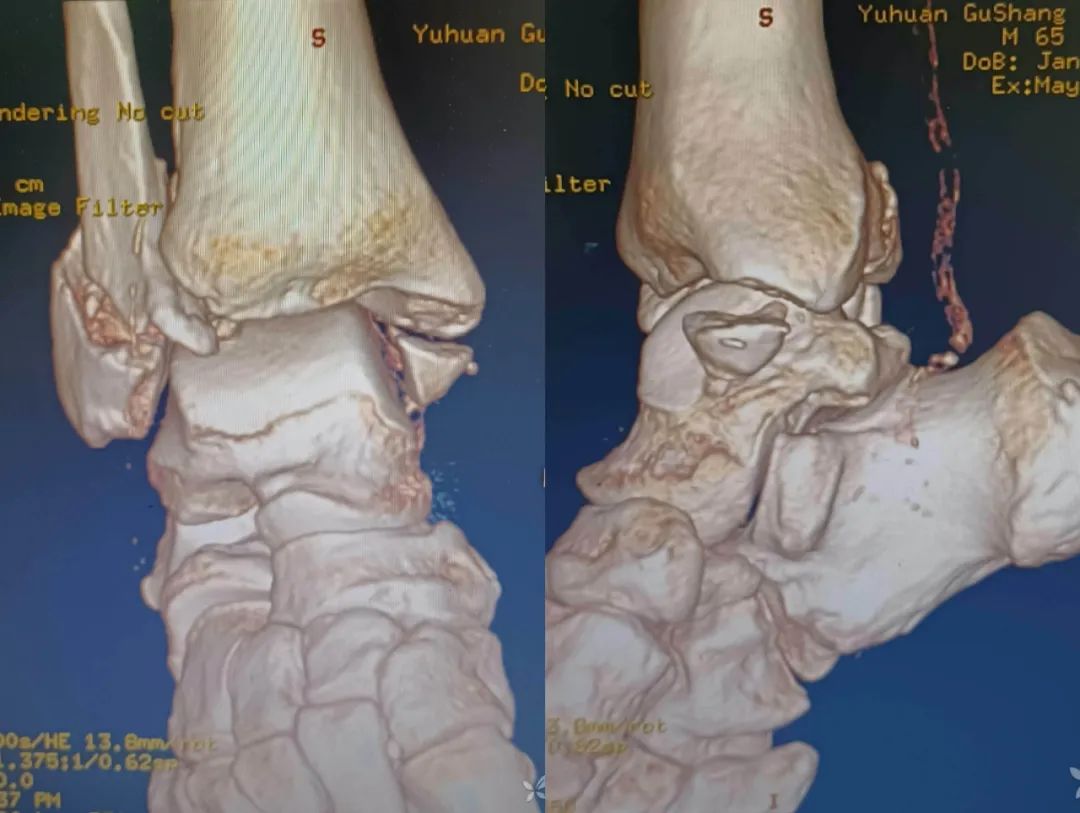

这是一例三踝骨折的患者。